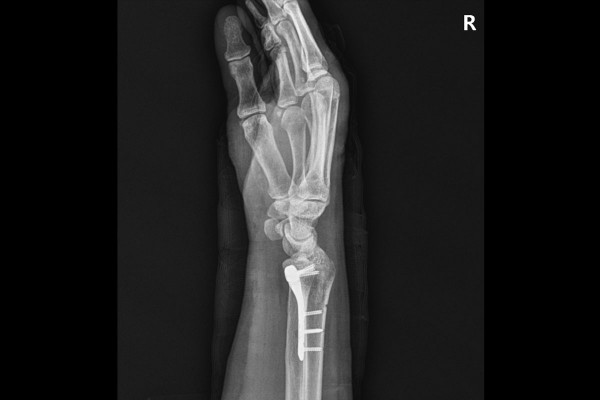

지참해오신 X-RAY 사진을 보면 손목 원위 요골이 골절된 것이 확인됩니다.